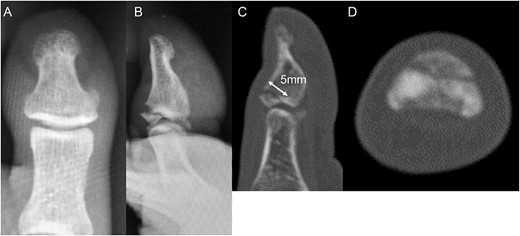

A 54-year-old man injured his right great toe while walking and wearing sandals. He complained of tenderness, swelling, and pain during motion. He could bear weight but could not actively extend the interphalangeal (IP) joint of the hallux. He was referred to our outpatient clinic 3 days after the injury. Physical examination revealed swelling, tenderness, and motion pain, and the patient could not extend the IP joint of the hallux. Plain lateral radiography and computed tomography revealed a displaced avulsion fracture of the dorsal base of the distal phalanx (Fig. 1). Surgery was performed under general anesthesia after informed consent was obtained on posttraumatic day 11. A Y-shaped incision was made at the center of the dorsal IP joint, and the displaced bony fragment was attached to the extensor hallucis longus (EHL). The IP joint was temporarily fixed with a 1.6 mm Kirschner wire, and the fragment was repositioned and fixed with two 1.5 mm cortical screws (APTUS® Hand, Medartis, Basel, Switzerland). A 4-0 FiberWire® (Arthrex, Naples, FL, USA) was fastened as an augmentation proximally to the EHL tendon and distally to the periosteum of the distal phalanx in a figure eight (Fig. 2). Postoperatively, the ankle was externally fixed in dorsiflexion from the leg to the toe, and heel loading was permitted. A total of 4 weeks after surgery, the Kirschner wire was removed to allow active motion of the IP joint of the hallux, and weight bearing was allowed on the hallux 5 weeks postoperatively. Plain radiographs taken 3 months after surgery confirmed bone healing (Fig. 3). A total of 20 months postoperatively, the patient acquired normal function, and the range of motion of the affected IP joint ranged from −3° to 30°, with no difference from the unaffected side (Fig. 4). Skin necrosis or nail deformities were not observed.

Plain radiographs (A) anterior–posterior view and (B) lateral view show an avulsion fracture of the dorsal base of the distal phalanx. Plain computed tomography (C) sagittal slice and (D) axial slice reveals an avulsion fracture of the dorsal base of the distal phalanx similar to the plain radiograph. Additionally, the fracture length line of the fragment was 5 mm.

Operative findings (A) showed a bone fragment attached to the EHL (arrowhead) and (B) fixed with two screws (arrows). (C) Suture augmentation technique with FiberWire® (dotted line) proximally sutured to the EHL and distally sutured to the periosteum.